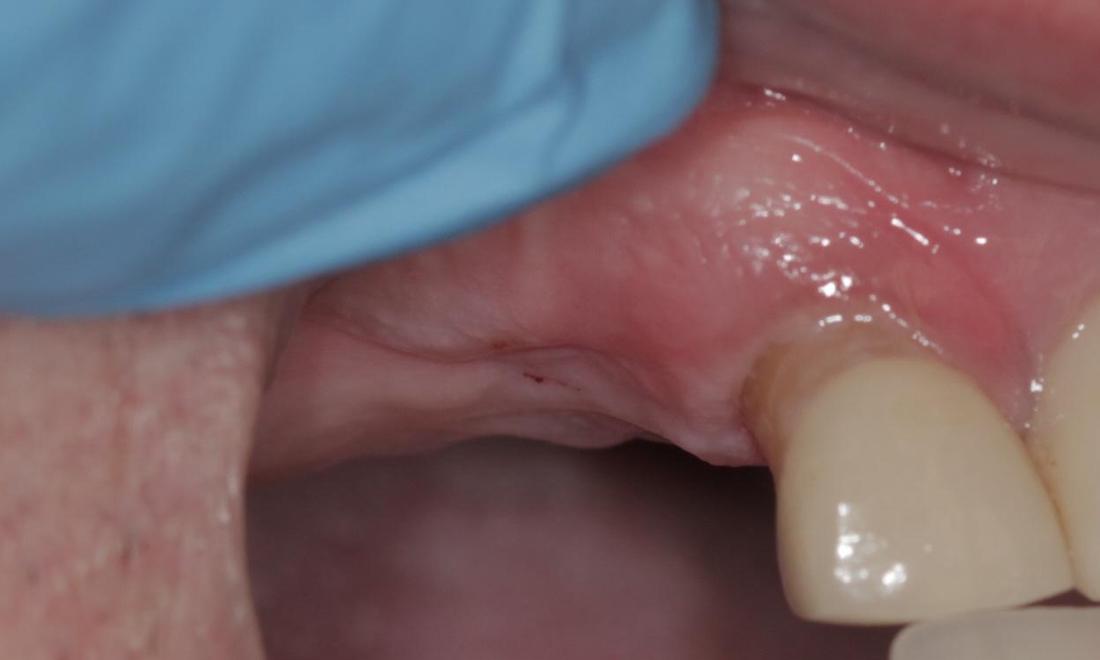

Mini Implant Bridge

This patient had been wearing a removable partial denture for years and was not happy with it. He complained of it moving while he chewed, and said he could not eat many of the foods that he enjoyed. After careful planning, 5 mini dental implants were placed, and a custom bridge was cemented into place. He is now able to chew food again on that side, and he does not have to worry about removing his teeth at night before bed. He called the day after the implants were placed to let us know he was on his way out to go fishing!